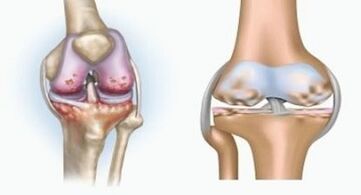

Arthritis

Arthritis is an inflammation of the connective tissue - a synovial membrane that contains many vessels and provides lymphatic flow.The inflammatory process leads to disruption of the nutrition of the joint tissues, resulting in the production of joint lubrication - the synovial fluid is limited.

Arthrosis

Arthrosis is a degenerative-dystrophic process associated with the destruction of the cartilage tissue of the joint.The cartilage is gradually destroyed, dry, the distance between the bones of the joint decreases, which is the cause of the pain.In severe forms, destruction affects the bones.They become more refined, lose their density, become fragile.